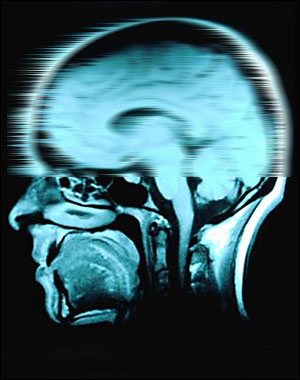

¿O borrar

memorias? ¿ha llegado la innovación digital al punto en el que se pueden crear recuerdos artificiales?

Hasta ahora estos temas han sido tratados sólo en la ciencia ficción. En "Eterno Resplandor De Una Mente Sin Recuerdos", por ejemplo, existe una empresa llamada Lacuna que se dedica a eliminar recuerdos que no son placenteros.

En un filme más reciente, El Origen (Inception, en inglés), los protagonistas son capaces de sembrar una idea en el subconciente de una persona.

Pero según Aza Raskin, Líder Creativo para Firefox de Mozilla y especialista en comportamiento de usuarios en internet, estas ideas podrían convertirse en una realidad gracias una combinación de publicidad y redes sociales.